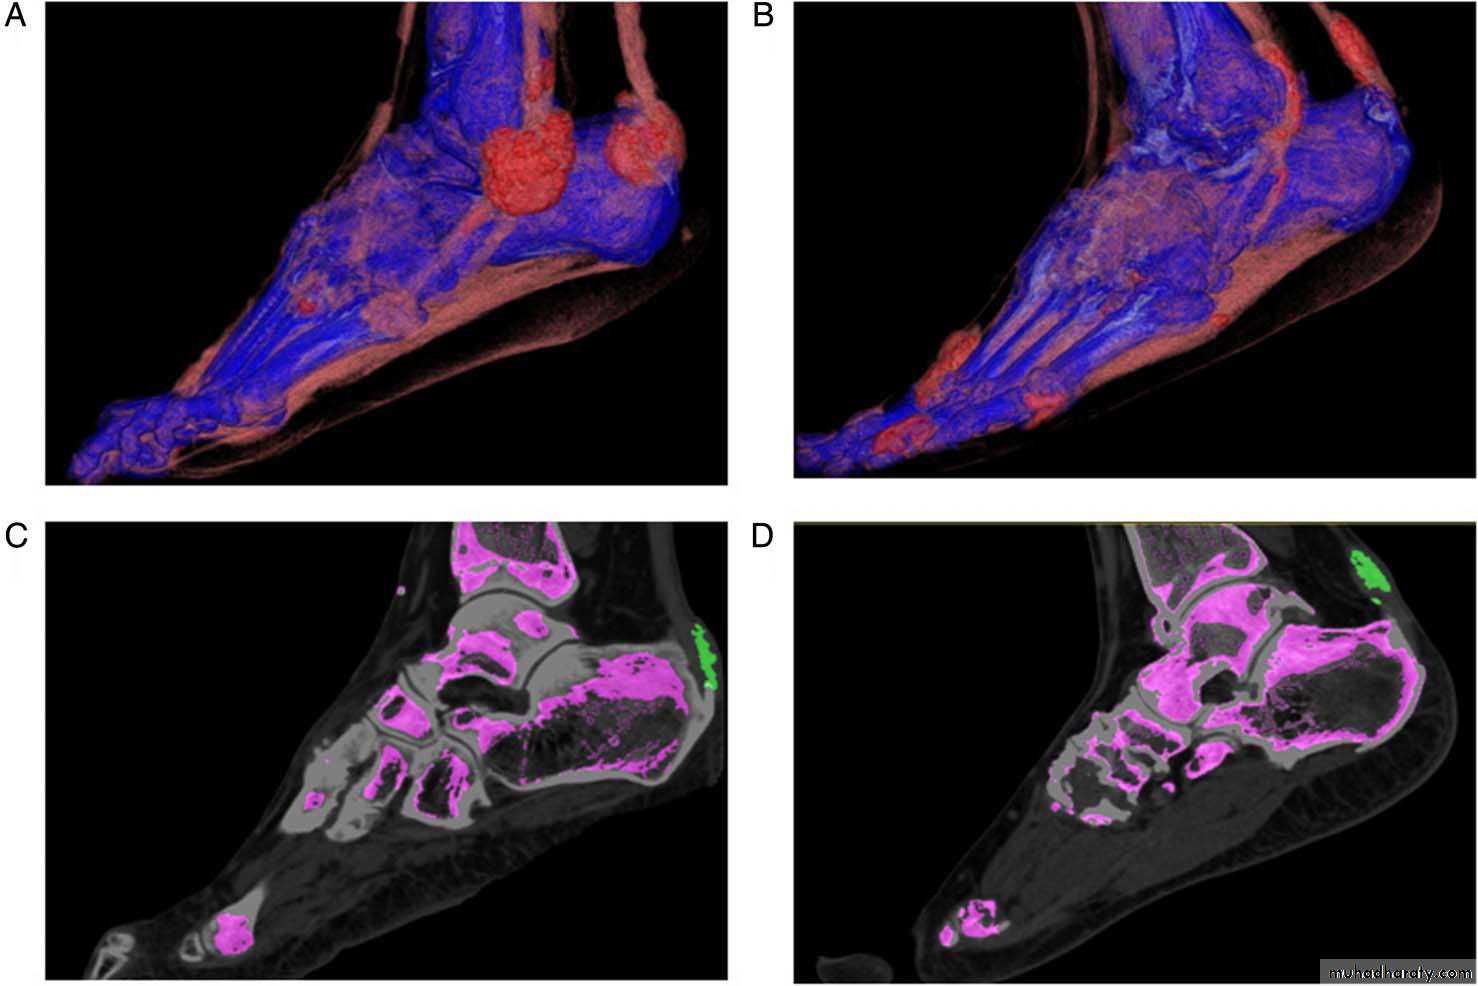

dual-energyCT images showing involvement oftendons in two patients withtophaceous gout. (A) and (B) showthree-dimensional volume-renderedimages demonstrating monosodiumurate (MSU) crystal deposition in theAchilles and peroneal tendons in bothpatients. (C) and (D) Two-dimensionalsagittal images confirming MSU crystaldeposition (green) at (C) the Achillesenthesis and (D) within the body ofthe Achilles tendon.

Dual energy CT images of urate deposits in patients with acute gout symptoms.